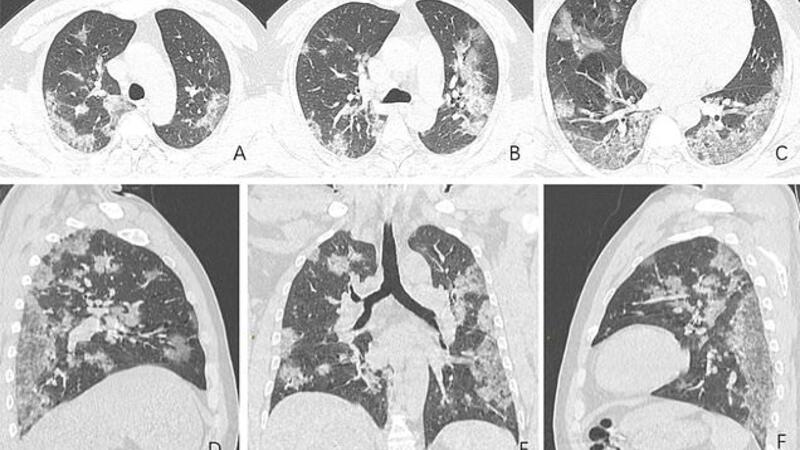

X-ray images and CT scans including those of a Chinese man, 44, who died from coronavirus show how the disease ravages its victims' lungs.

The scans show white patches in the lower corners of the lungs which indicates what radiologists call ground glass opacity - the partial filling of air spaces.

The scans, released by the Radiological Society of North America, show how the fluid in the spaces of the man's lungs became more pronounced over time, as evident when comparing image A to image F.

The CT scans of a 54-year-old woman who caught the coronavirus after travelling to Wuhan, China, show the same partial filling of air spaces.

The woman was diagnosed with severe pneumonia caused by the virus after suffering from a fever, cough, fatigue and chest congestion for a week, and she was given oxygen and antibiotics.